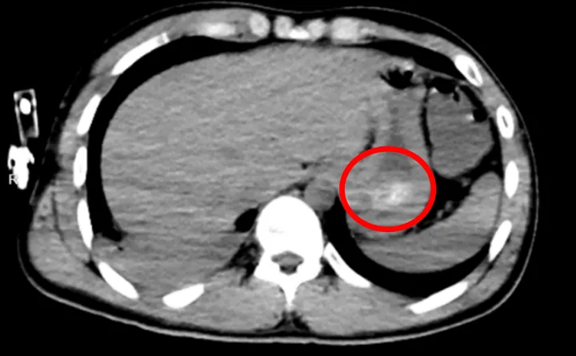

Chụp CT đã cho thấy nguyên nhân: trong dạ dày của anh tồn tại một khối lớn kết dính từ các viên thuốc, gọi là “bezoar thuốc” (khối thuốc đông kết). Không chỉ vậy, anh còn bị viêm phổi hít do nôn trớ trong lúc ý thức kém, khiến tình trạng càng nguy kịch.